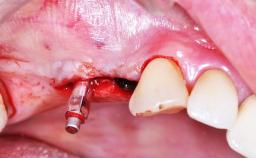

Implant Placement with Simultaneous SFE: Transcrestal Technique with DBBM

Clinical Case Report

Implant Placement with Simultaneous Sinus Floor Elevation (Lateral Window Technique)

Clinical Case Video